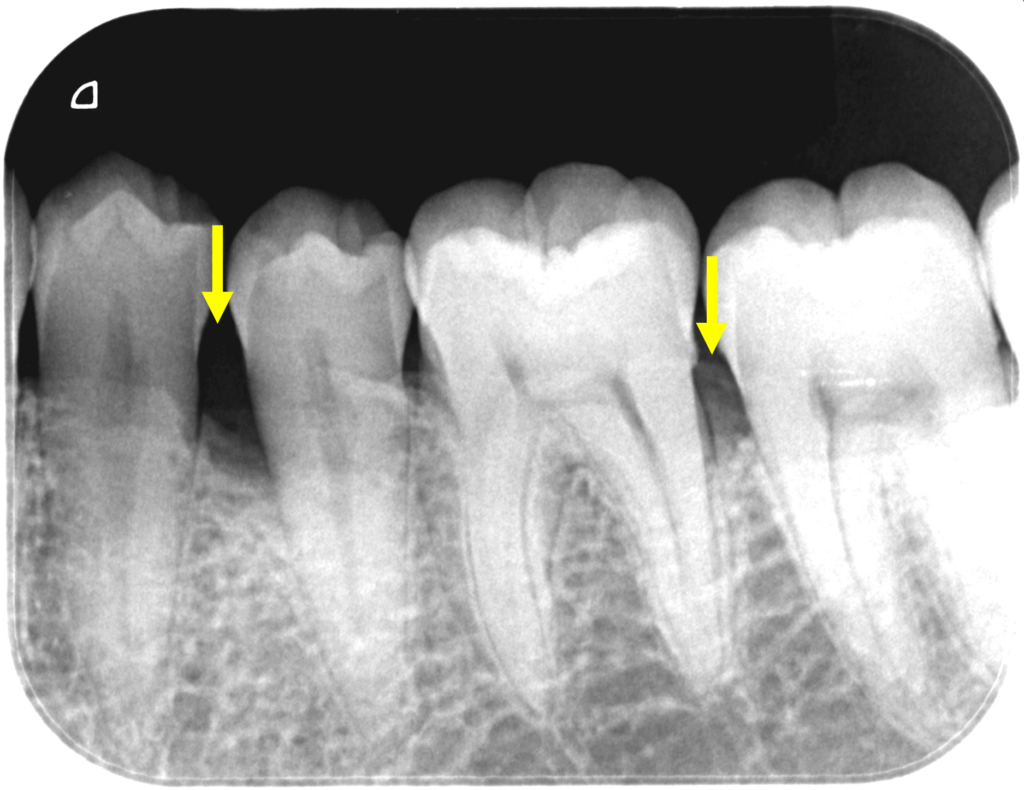

46歳男性です。

黄色い矢印のところの骨(歯槽骨)が溶けています。

歯周再生材料と人工骨を併用した歯周再生外科を行いました。

歯肉を開いて歯肉の中の歯根面に付着している歯石や骨(歯槽骨)が溶けている中の不良肉芽(正常でないない軟組織)を徹底的に除去し、

再生材料と人工骨と填入し、縫合しました。